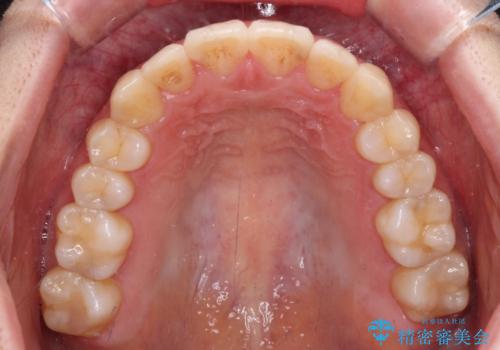

【モニター】前歯の前突感とクロスバイトをインビザラインで改善

- 前歯の突出感とクロスバイトが気になり、インビザラインによる矯正治療を希望して来院された患者様です。

上顎側切歯(上の真ん中から2番目の歯)が舌側転位している場合、インビザラインでは仕上げきれないことが多く、更には無理して動かそうとすると歯髄壊死を起こすリスクが高いと言われています。

インビザラインで歯列を移動する前に、上顎前歯をワイヤー矯正で整え、その後上下歯列をインビザラインにて矯正治療を行うこととしました。

舌側転位している側切歯特有の、切縁の位置が不揃いであったり、根元が内側に引っ込んだ状態であったりという、インビザライン独特の仕上がりになることなく、きれいに整った歯列とすることができました。